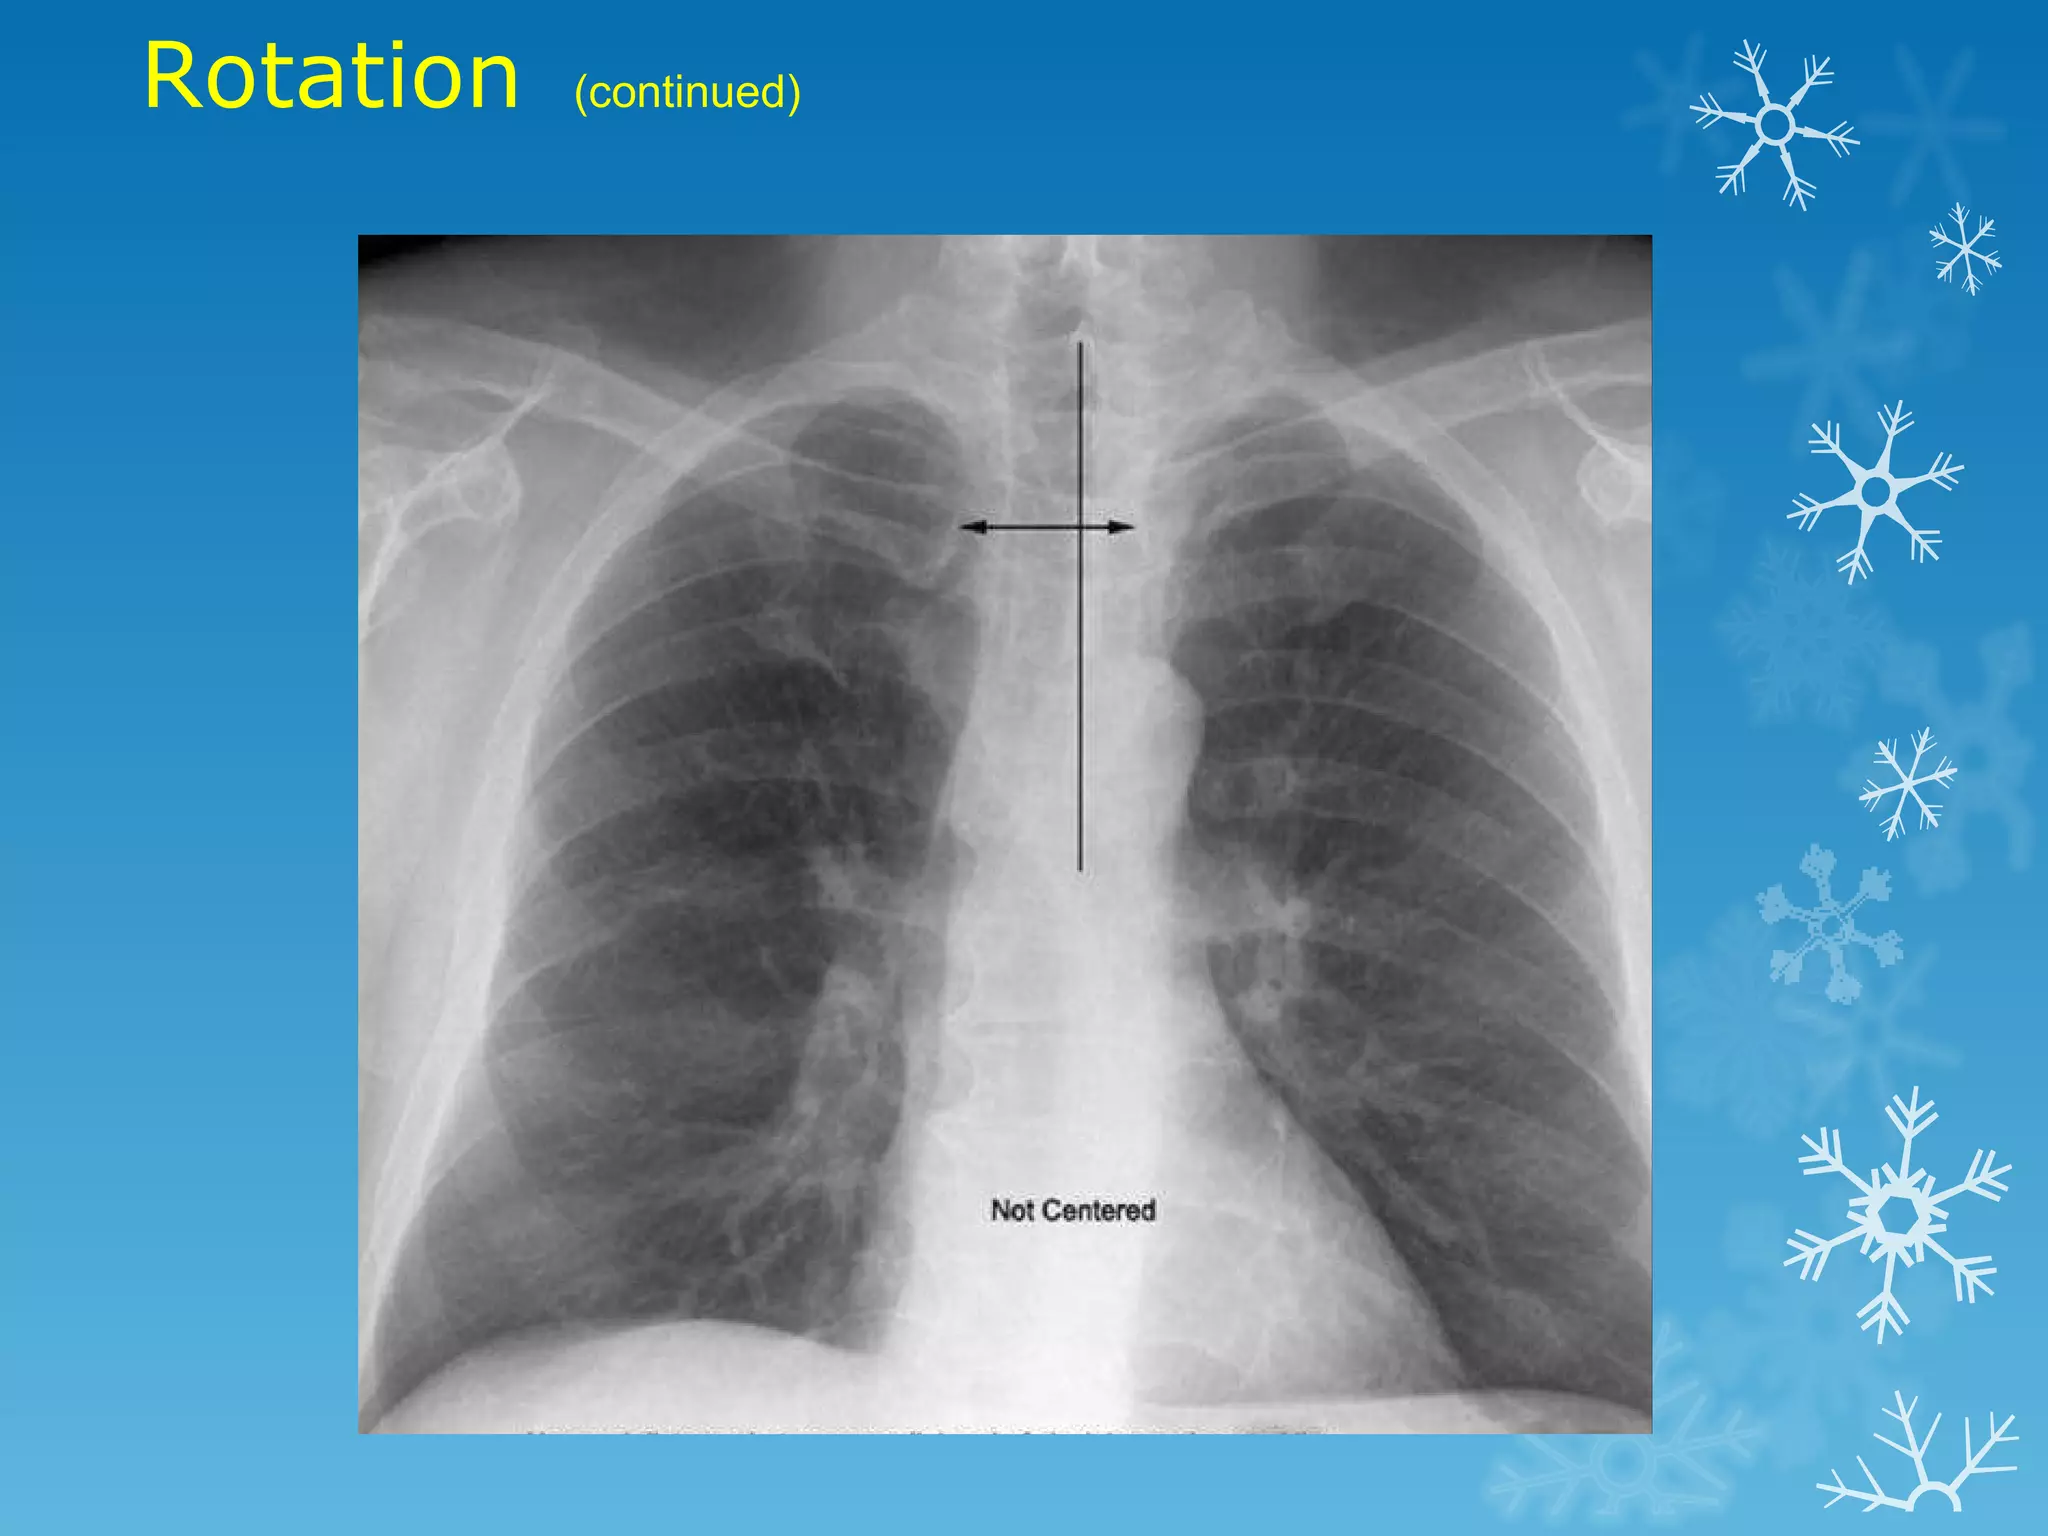

This document discusses chest x-ray interpretation and provides guidance on evaluating x-rays. It explains that tissue density determines how an x-ray beam penetrates, with denser tissues appearing whiter and less dense tissues appearing blacker. It also outlines different chest x-ray views and factors to consider like patient orientation, age, gender, and rotation. Abnormalities are described as appearing too white, too black, too large, or in the wrong place. The document stresses a systematic approach of identifying, localizing, describing lesions, and providing differential diagnoses.